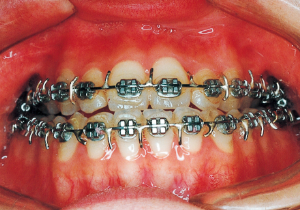

2 After Phase 2 Treatment 5-9-’92

16 5-9-’92 After Phase 2 Treatment

17 8-15-’94 After Retention 14 years and 7 months after start of treatment

Retention period: 2 years 5 months

Total Management Period: 15 years from 8 years 1 month to 23 years 1 month